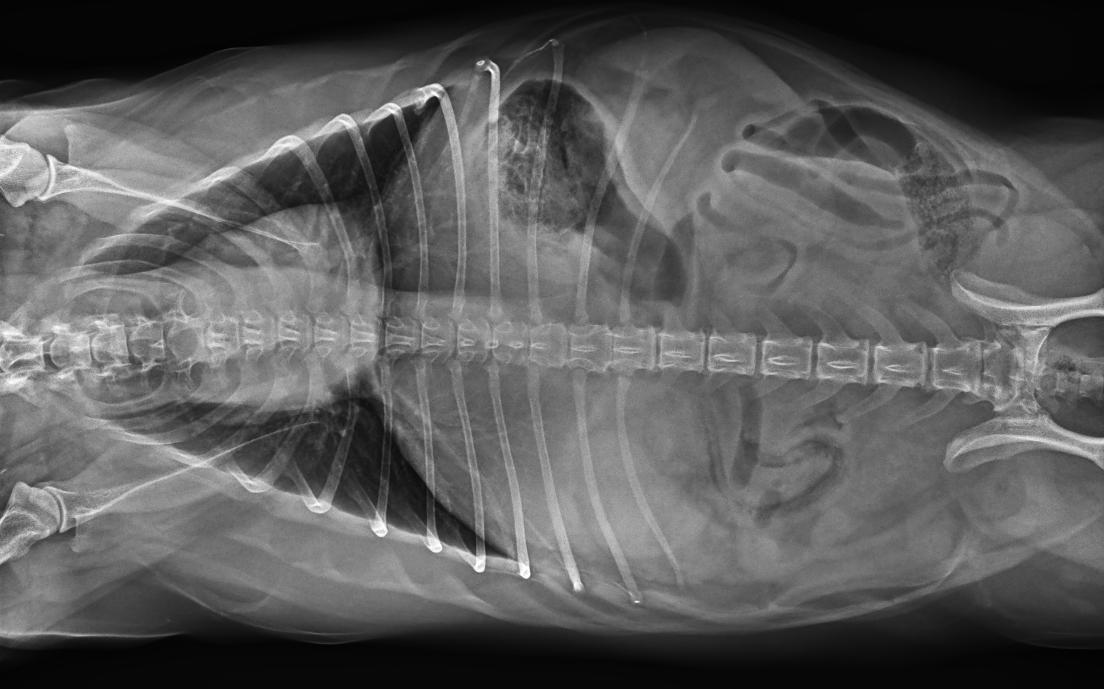

● 17*17大尺寸平板探測器,獲得高質(zhì)量圖像

● 優(yōu)異的空間分辨率及信噪比,提升圖像質(zhì)量

● 采用線噪聲消除技術(shù),使成像質(zhì)量提升40%

● 智能高效的圖像處理軟件,大幅提升圖像質(zhì)量